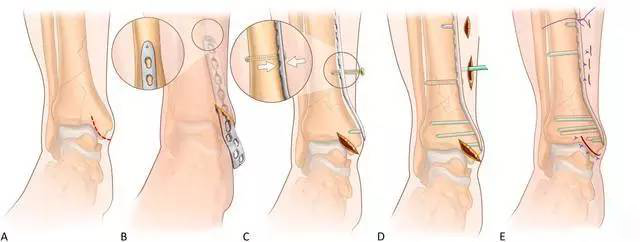

图3 前内侧 MIPO 入路

腓骨切口选择骨折平面切开,1/3 管型钢板固定。胫骨内侧 MIPO 切口:跨过内踝尖自近端前侧向远端后侧做斜行长约 3 cm(如图 3A)切口,该斜行切口允许延伸显露前方干骺端和关节面,能直接复位任何简单关节内骨折。

在钢板固定前,可由内向外拧入拉力螺钉实现关节面加压,骨折存在其他方向成角可选择第2 个小切口显露。

通过插入剪刀在软组织下、骨膜上建立通道,钢板远端拧入导向器当「把手」插入钢板(如图3B),皮外触摸可以评估钢板行进方向。

钢板远端位置:至少占据内踝的1/2,但最远不超过内踝尖,C 臂透视确定位置后克氏针临时固定,近端小切口显露钢板近端,同时必须确保骨折复位,触摸或 C 臂机透视确定后克氏针临时固定近端钢板。

C 臂机透视确定踝关节前关节面的复位情况:若复位满意,在植入非锁定螺钉时需要注意维持骨折的复位,因使用非锁定螺钉时可能导致钢板未贴合骨面处的骨折移位;若复位不满意,拧入一枚非锁定「复位」钉间接复位骨折(如图 3C)。

钢板远近端拧入锁定钉,骨折区域不打钉(如图3D)。若使用复位钉,最后取出复位钉,避免过于接近骨折端,常规关闭切口。若内侧 MIPO 切口无法复位骨折时,可延伸切口行有限切开复位。